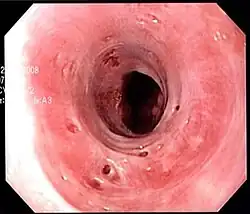

| Endoscopic image of esophageal intramural pseudodiverticulosis demonstrating the flask-like outpouchings of the esophageal wall. | |

Esophageal intramucosal pseudodiverticulosis is typically diagnosed at the time of endoscopy of the esophagus. Endoscopy shows evidence of the pseudodiverticulae, which are typically numerous, appear like pits in the wall, and may be preferentially located in the upper esophagus.[3][5] The mucosal lining of the esophagus may be inflamed, and this can be seen on endoscopy or biopsy; the mucosa, however, may also be normal if esophagitis is not the cause of the pseudodiverticulosis. The condition must also be excluded from esophageal cancer, which may be done at the time of endoscopy, or which may require esophageal biopsy.[3]